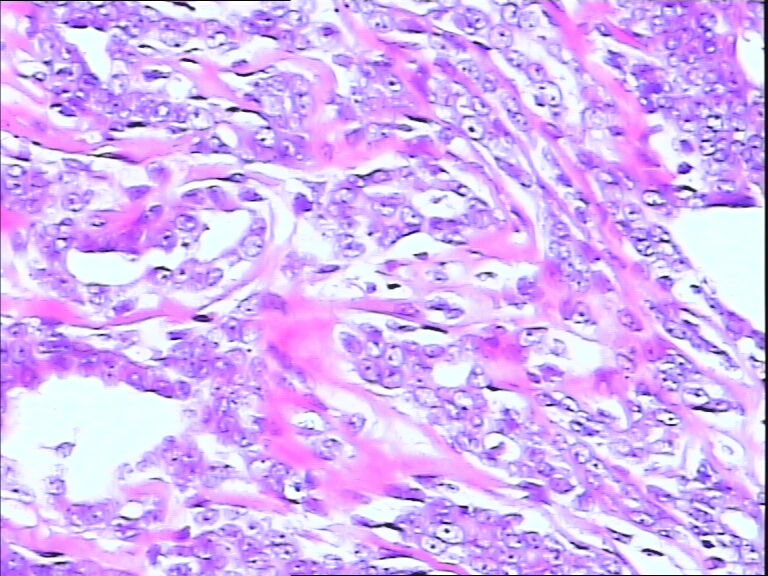

B3785左乳头包块!

42y

左乳头有3mm结节

灰白不整形组织一块:0.7*0.5*0.4

• 左乳头包块!图3

图3

标签:导管内乳头状肿瘤

导管内乳头状瘤,导管上皮不典型增生。

导管内乳头状瘤,局灶伴不典型增生。

导管内乳头状结构,细胞无异型性,诊断导管内乳头状瘤。